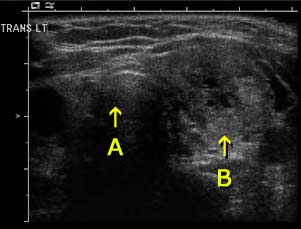

Sonogram of the left lobe of the thyroid gland in cross section (transverse section) shows a heterogeneous nodule.

A: Trachea

B: Left lobe mass